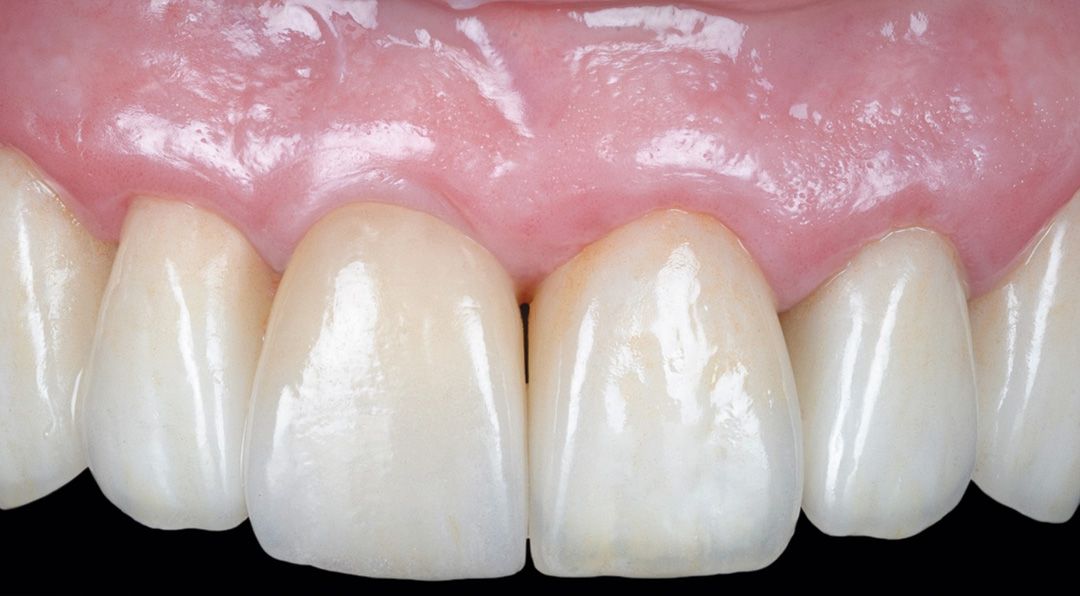

Four months post-placement, the implant site exhibited stable soft tissue contours and full graft integration. A screw-retained lithium disilicate crown was delivered and bonded to a customised anodised titanium abutment. Radiographs confirmed excellent osseointegration and bone preservation. Post-operative care included chlorhexidine 0.12% gel application twice daily for 14 days. The patient expressed high satisfaction with the aesthetic result, and no recession or tissue shrinkage was observed during the healing period.